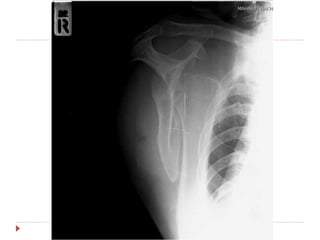

 Film right shoulder AP , transcapular

 Film right humerous AP , lateral

Right anterior shoulder dislocation

with avulsion fracture right greater

tuberosity

investigation  Film rightshoulder AP , transcapular  Film right humerous AP , lateral

Imp : Right anteriorshoulder dislocation with avulsion fracture right greater tuberosity